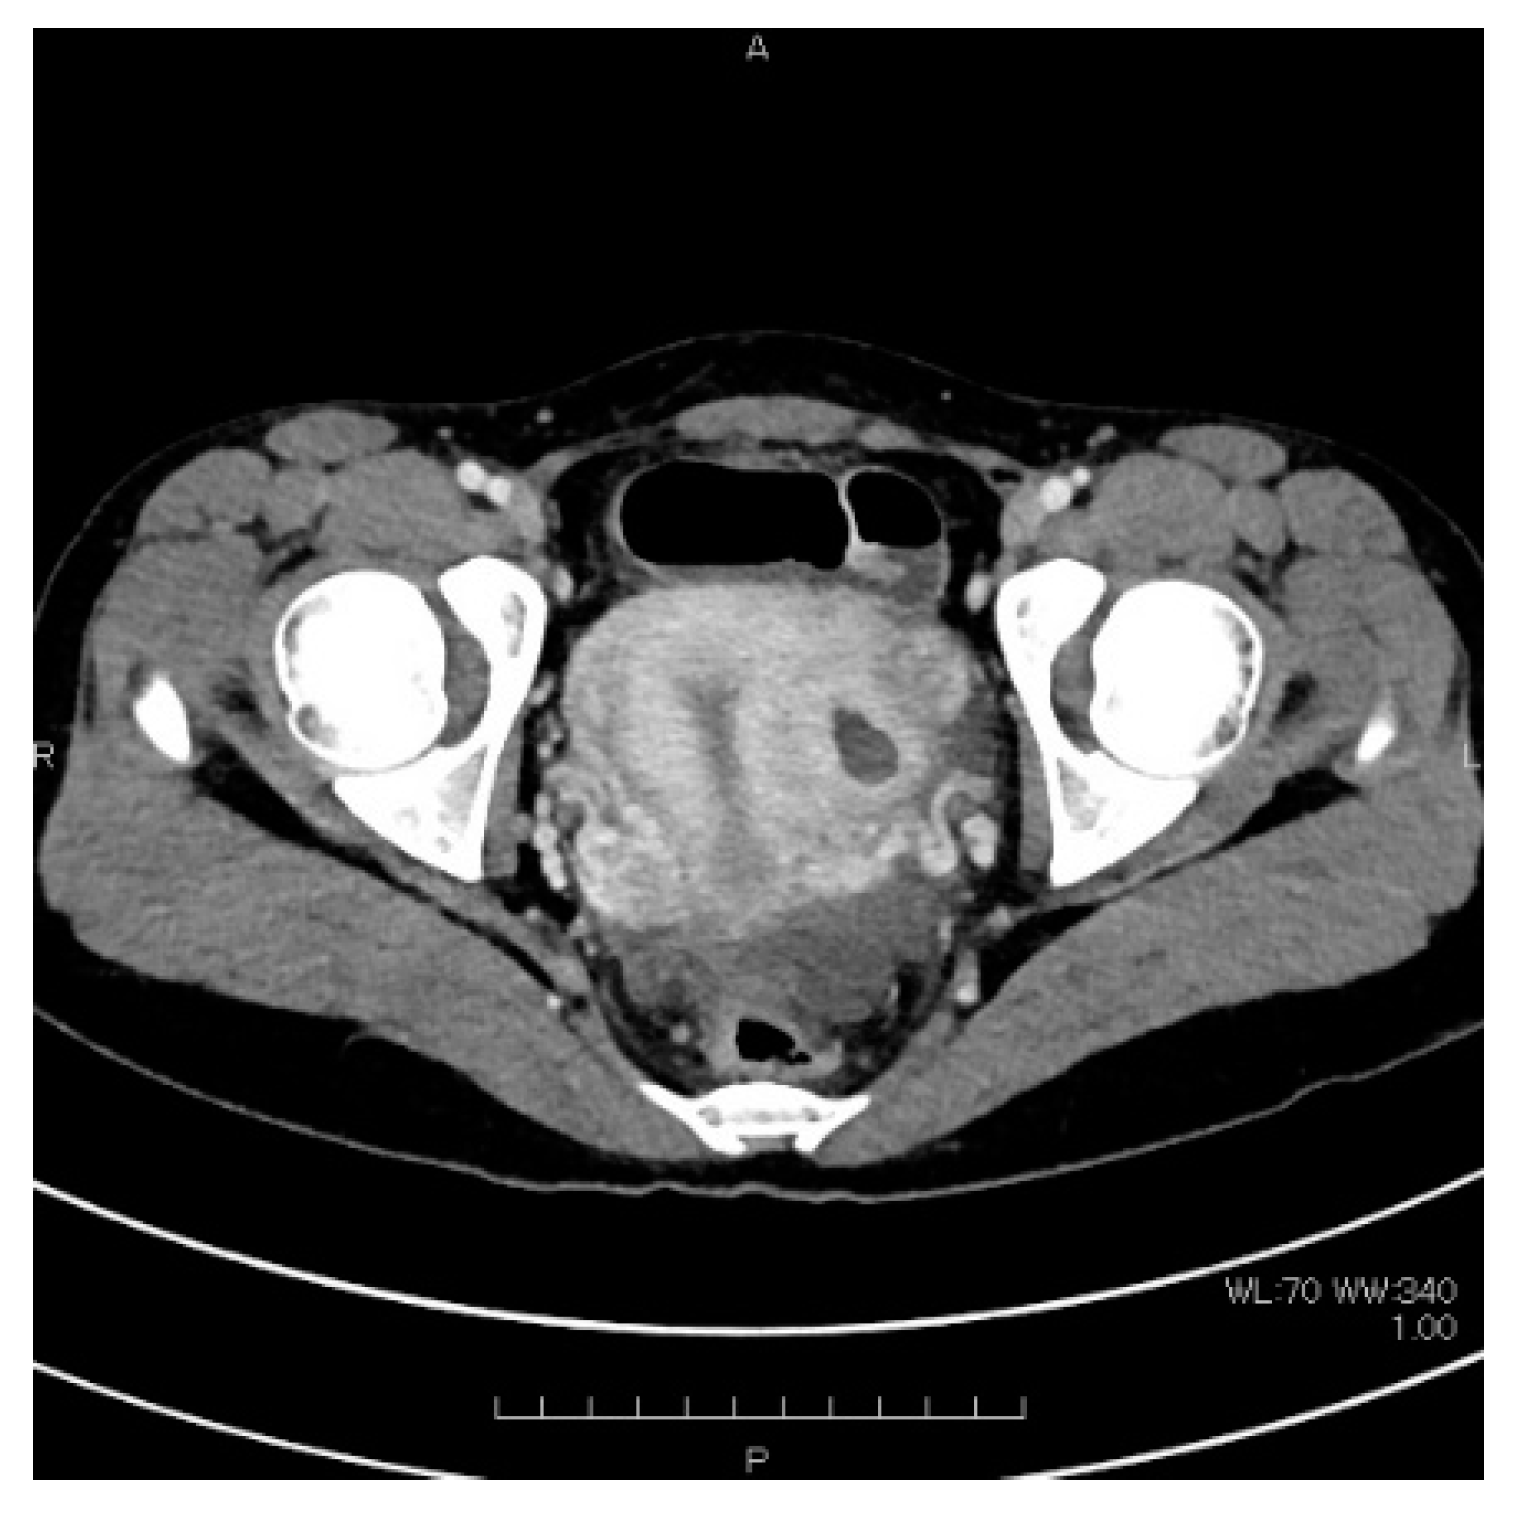

| This case | 22 | 0 | 0 | 15 | 36 | L | 51.9 | None | CT, MRI: None | Laparoscopy | 3 cm, lateral, left side | Harmonic Scalpel, scissors forceps | 2 layers using 0 PDS | 14 | 69 | few | 2 | Present study |